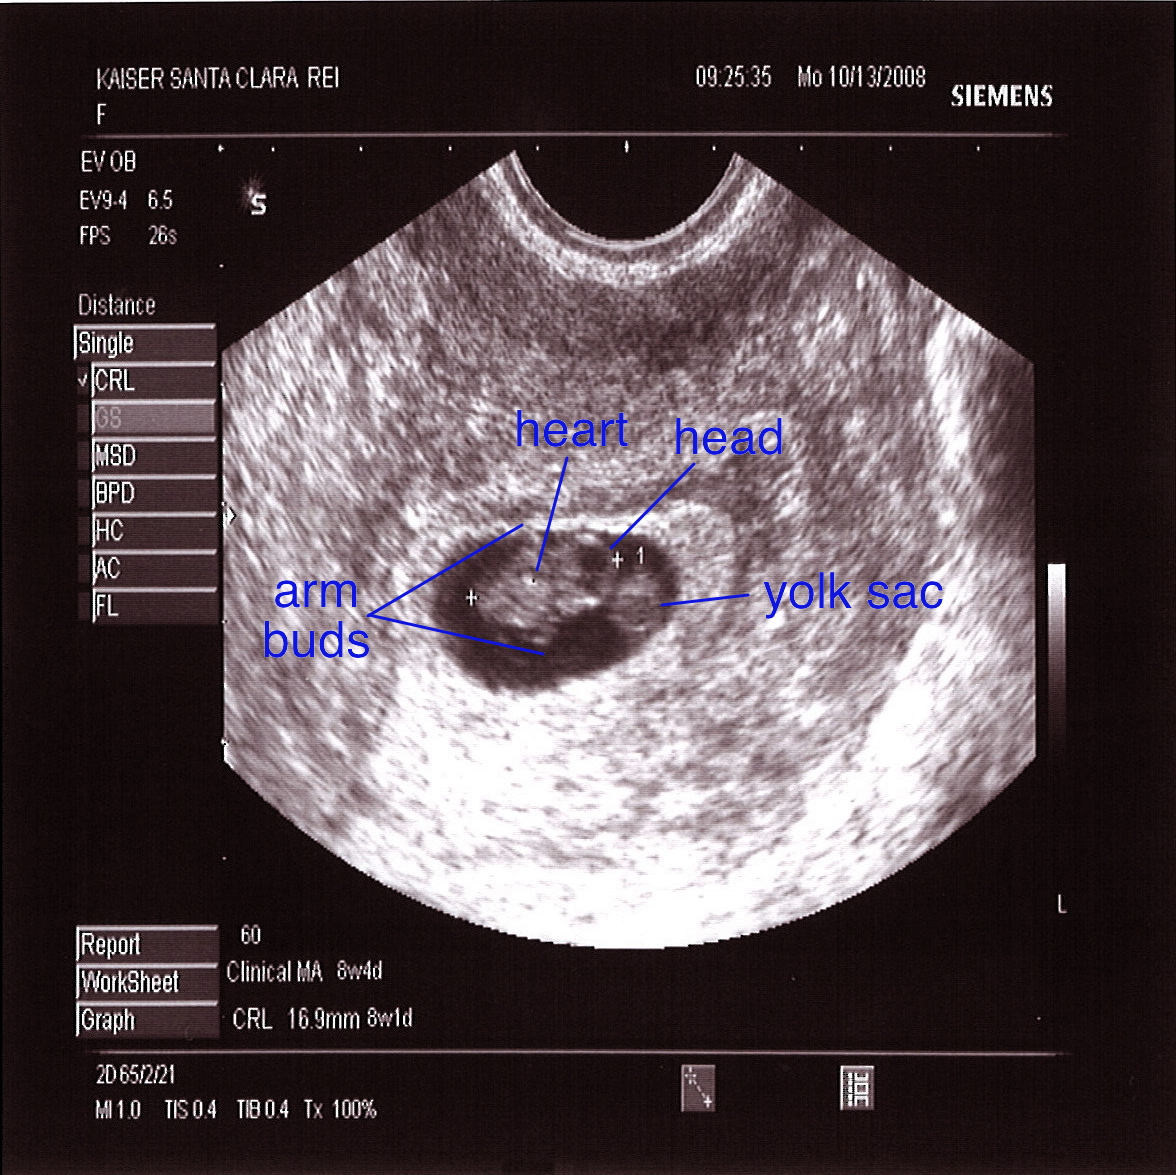

8 Weeks Ultrasound Scan – All Your Questions Answered – MyBump2Baby

Can You See Baby In Ultrasound At 8 Weeks – ababyw

8 Weeks 6 Days Pregnant – Precautions, What to Avoid, Baby Fetal Size …

8 Weeks Pregnant Ultrasound – Ultrasound at 8 weeks, 4 days | Ever …

The Pregnancy Diaries: I’m 8 weeks pregnant! – Life Education Council